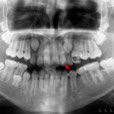

Paciente de sexo masculino de 9 años de edad, acude a la consulta para la evaluación radiográfica previa al tratamiento de ortodoncia ,clínicamente se aprecia alteración morfológica de la pieza 9 (2.2) . En la evaluación radiográfica se observa una proyección de tejido dentario en cara libre de pieza 9 (2.2)

La cúspide en talón es una hiperplasia anómala del cíngulo de un incisivo superior o inferior que da lugar a la formación de una cúspide supernumeraria. Es poco frecuente puede encontrarse en ambos sexos y afectar a la dentición decidua como permanente, su tamaño varia desde un cíngulo prominente hasta el de una proyección que puede llegar al borde incisal, se ha observado mayor incidencia en relación con el paladar hendido. Radiográficamente se superpone al incisivo y puede ser confundido con un diente supernumerario, para descartar esta posibilidad es necesario una variación en la angulación horizontal.